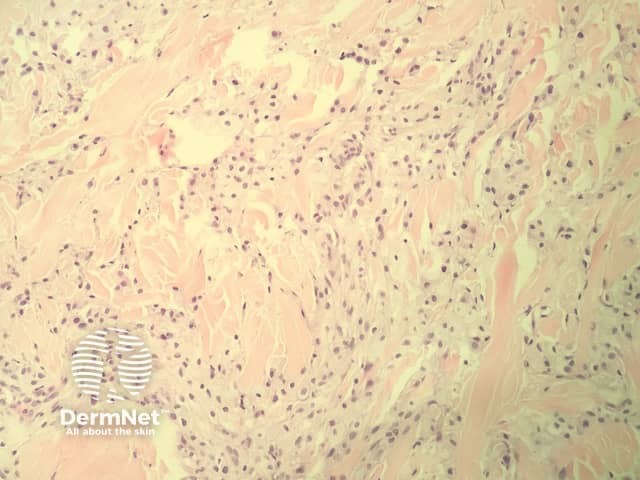

In eruptive xanthoma, the dermis contains a dense population of foamy histiocytes (histiocytes filled with lipid material as well as extracellular lipid (figures 1–3). There is often an associated acute and chronic inflammatory response (figure 4).

Figure 4